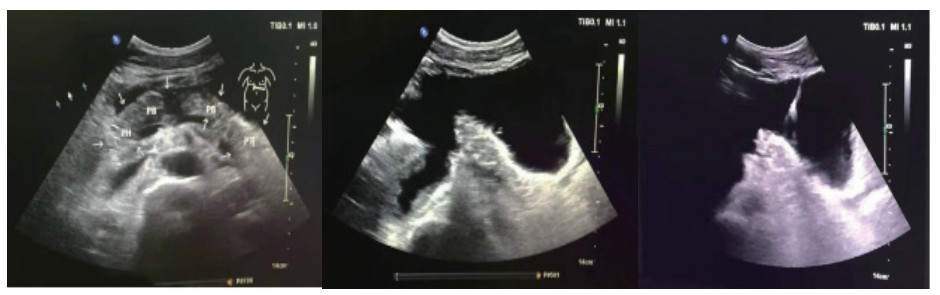

患者男,26岁,维吾尔族,以“高处坠落致腹部疼痛2 d”为主诉入院。患者于2019-03-26凌晨1时左右饮酒后不慎从2 M高处楼梯上摔下,伤及头部、腹部及腰背部,左侧面颊部见少量出血,当时神志状态不明,是否存在腹部及腰背部疼痛,无人知晓。至清晨8时左右,被家属发现俯卧于楼梯口,患者昏睡,周围未见呕吐物,楼梯上可见少量血迹,面颊部擦伤已结痂,呼唤能醒,自诉腹部及腰背部疼痛不适,无头痛、头晕,无恶心、呕吐,遂被立即送往当地县人民医院,CT检查后考虑“胰腺断裂”,给予输液治疗(具体不详),患者意识逐渐转清,可简单对答。为进一步治疗,于2019-03-26晚21:45转入阿克苏农一师医院。入院查体:体温37.1℃,呼吸20次/min,心率90次/min血压120/79 mmHg,腹部平坦,腹皮肤表面未见明显挫伤痕迹,未见胃型,未见肠型,未见蠕动波,无腹壁静脉曲张,未见手术瘢痕,全腹压痛,腹肌紧张,上腹部明显,反跳痛全腹存在,未触及液波震颤,未及腹部包块,肠鸣音减弱,1~2次/min。双肾区有叩痛,右侧明显。骨盆挤压试验(-)。急诊检查生命体征尚稳定,拟诊“腹部闭合性损伤:胰腺断裂?右肾动脉损伤、右肾坏死?”收入ICU。入院诊断:闭合性腹部损伤,胰腺断裂Ⅳ级(主胰管断裂)、弥漫性腹膜炎、右肾动脉损伤、右肾梗死。入院实验室检查:WBC:11.5×109/ L, N:92.1%, Hb 10.5 g,PCT:4.32 ng/mL。入院影像学检查:胸部+腹部增强CT(2019年3月2号晚21:45):右肺下叶炎症,右侧胸腔少量积液,双侧局部胸膜肥厚,胰腺断裂伴周围低密度病灶,考虑假性囊肿形成,右肾动脉损伤,右肾无灌注,腹腔、盆腔积液(考虑血性),腹腔内局部脂肪间隙浑浊,考虑腹膜炎,提示:腹腔内部分肠管明显扩张并积气。此报告为危急值报告!治疗经过:入住ICU,先期放置胃管行胃肠减压,4 d后起经鼻空肠营养,逐渐加量至全量;主要药物泮托拉唑抑酸护胃,生长抑素抑制胰酶分泌,头孢他定+甲硝唑抗感染;本案例入院时创伤发生已过24 h,右肾不显影提示肾动脉梗死造成右肾梗死,介入再通已过时间窗,故放弃介入,不做进一步处理;入院当天腹部增强CT提示胰腺断裂Ⅳ级,胰管完全离断,胰头与胰体尾明显分离,腹腔积液以左中上腹、左下腹居多,腹膜刺激征遍及全腹,按传统观点手术指征明确。但血流动力学稳定,读CT片并完成MRCP后,排除空腔脏器破裂,明确积液集中于上腹部和左下腹,大胆尝试在创伤ICU支持下行非手术治疗。2019-03-29患者行B超检查,示腹腔积液,积液相对集中于左中上腹和左下腹(图 1)。B超定位引导下行左上腹和左下腹穿刺引流(图 2),引出液体性状淡血性,引流效果明显,患者病情较前好转,但血象仍较高,予头孢他啶和甲硝唑抗感染。入院4 d后腹胀缓解即行经鼻空肠营养,以后视腹胀情况逐日加量,5 d后出ICU,因经济问题普通病房住院10 d,带管出院。出院1个月后来院行ERCP术置管困难,放弃置管内引流,继续腹腔引流管回家,未做任何处理。3个月后腹腔引流管自行脱落,6个月后来院复查CT(图 3),胰腺外形基本恢复正常,腹腔无积液,饮食正常,自诉家中腹腔引流管脱落后无任何不适。

| 图 1 患者入院48 h后胰腺彩色超声影像:肠间有积液 |

| 图 2 患者左中上腹部和左下腹穿刺引流 |